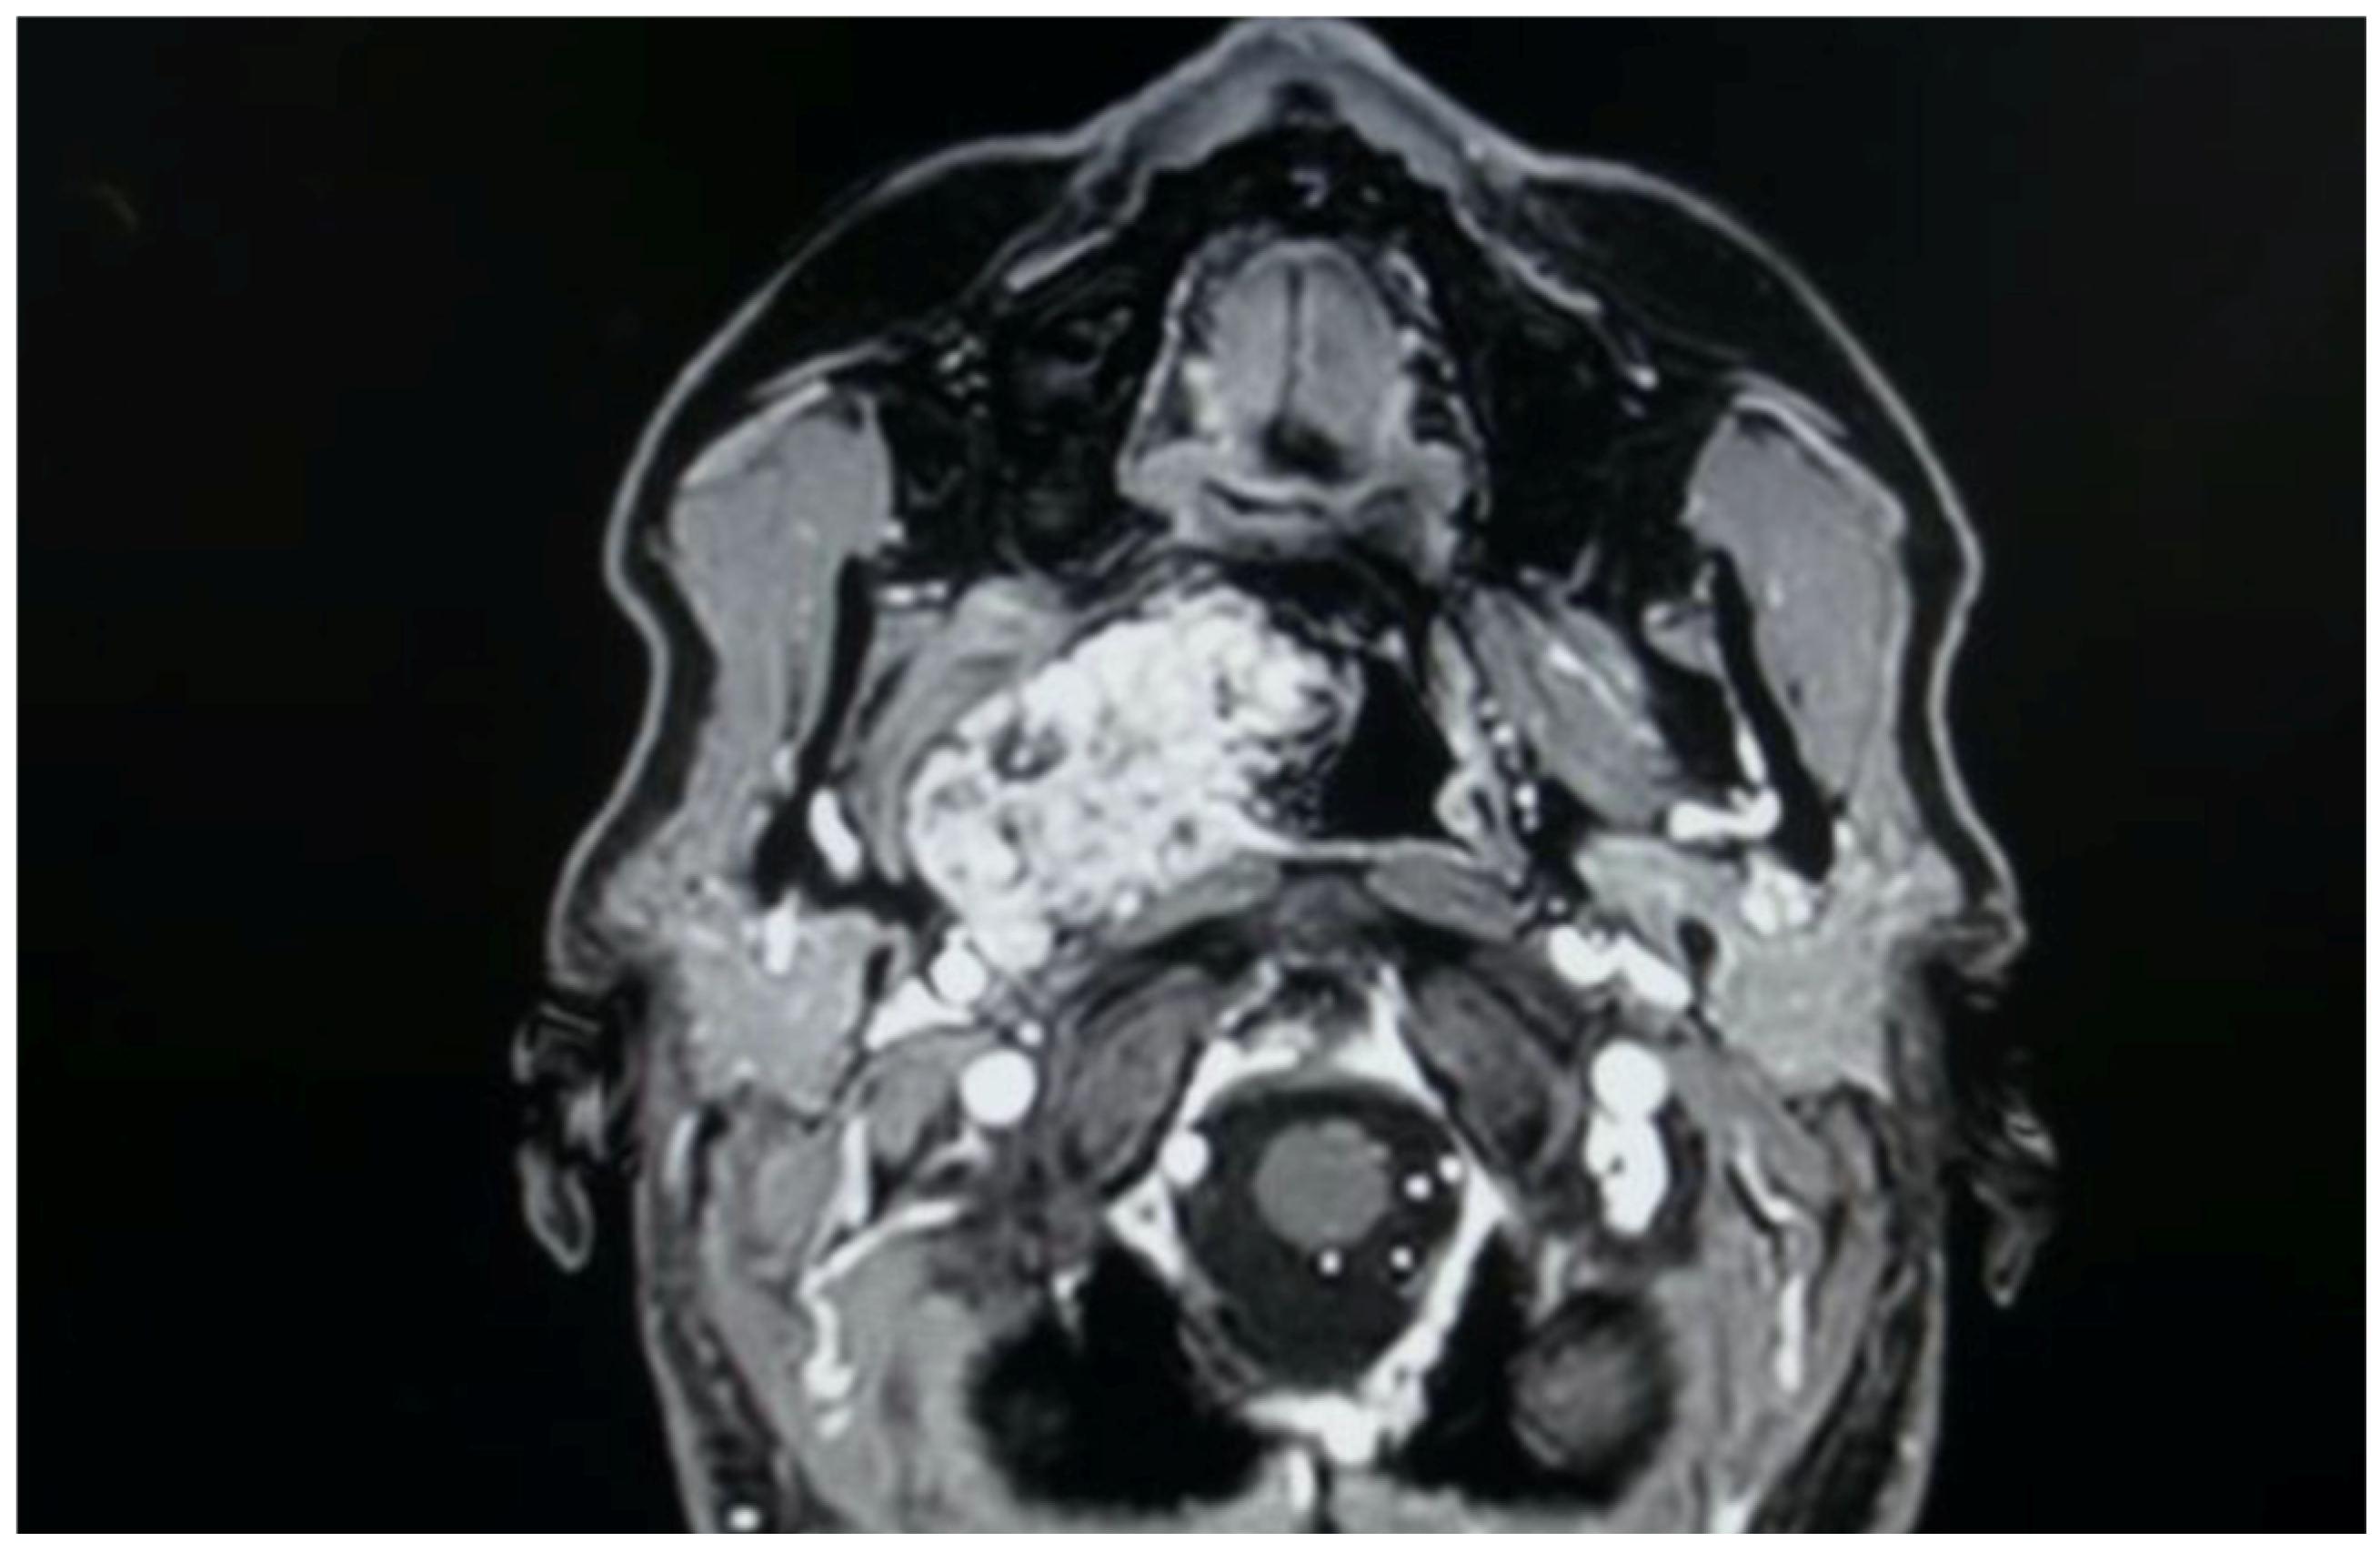

The treatment of PPS pathology represents a territory where both transoral approaches have been proposed, even as alternatives to classic open transcervical or transcervical–transparotid approaches [1,5]. Numerous authors in recent years have described the safety and efficacy of these transoral techniques, demonstrating favorable outcomes in terms of postoperative pain, length of hospital stay, and aesthetic results compared to traditional external approaches [1,5]. Our presented case series, as highlighted in the summary table, corroborates these findings. Specifically, in our cohort, postoperative pain was never significant (managed with as-needed paracetamol when required), hospitalization was brief, and no patient necessitated an external incision, offering advantages in terms of both postoperative recovery and aesthetic outcomes. This shift towards the selection of a transoral corridor is gaining momentum; however, it is crucial to emphasize several aspects. The meticulous evaluation of the patient and the tumor is paramount when considering a transoral approach [1,5,6,7]. A thorough clinical and radiological assessment is essential, particularly to evaluate the benign or malignant characteristics of the lesion, its vascularity in the case of vascular lesions, and its relationship with major neck vessels, which could lead to critically challenging management issues if these evaluations are not diligently performed [1,5,6,7]. Many case series highlight that tumors removed via these approaches are predominantly benign, non-vascular, and encapsulated lesions, such as pleomorphic adenomas and schwannomas. Malignant tumors, where open approaches are often more appropriate, and vascular tumors like paragangliomas, due to the high risk of intraoperative hemorrhage and subsequent difficult management via a transoral route, are typically excluded from these techniques [1,5]. Consequently, magnetic resonance imaging (MRI) with contrast enhancement frequently serves as the primary imaging modality to confirm clinical assessment and guide the decision-making process for selecting suitable candidates for transoral surgery [1,5]. In this presented multicentric case series, all benign and encapsulated lesions removed via the transoral route exhibited a favorable pattern of major vessel displacement. Specifically, the seven true PPS tumors, comprising five pleomorphic adenomas originating from ectopic salivary tissue, minor salivary glands, and the deep lobe of the parotid gland, consistently demonstrated a posterior displacement of the major neck vessels and an anteromedial displacement pattern of the parapharyngeal fat, a characteristic typically associated with benign lesions of the true PPS [1,5]. Figure 3 illustrates a pleomorphic adenoma from our case series, originating from accessory salivary glands of the true PPS, demonstrating this characteristic pattern of posterior displacement.

Figure 4. PPS schwannoma showing atypical posterior major vessels displacement.